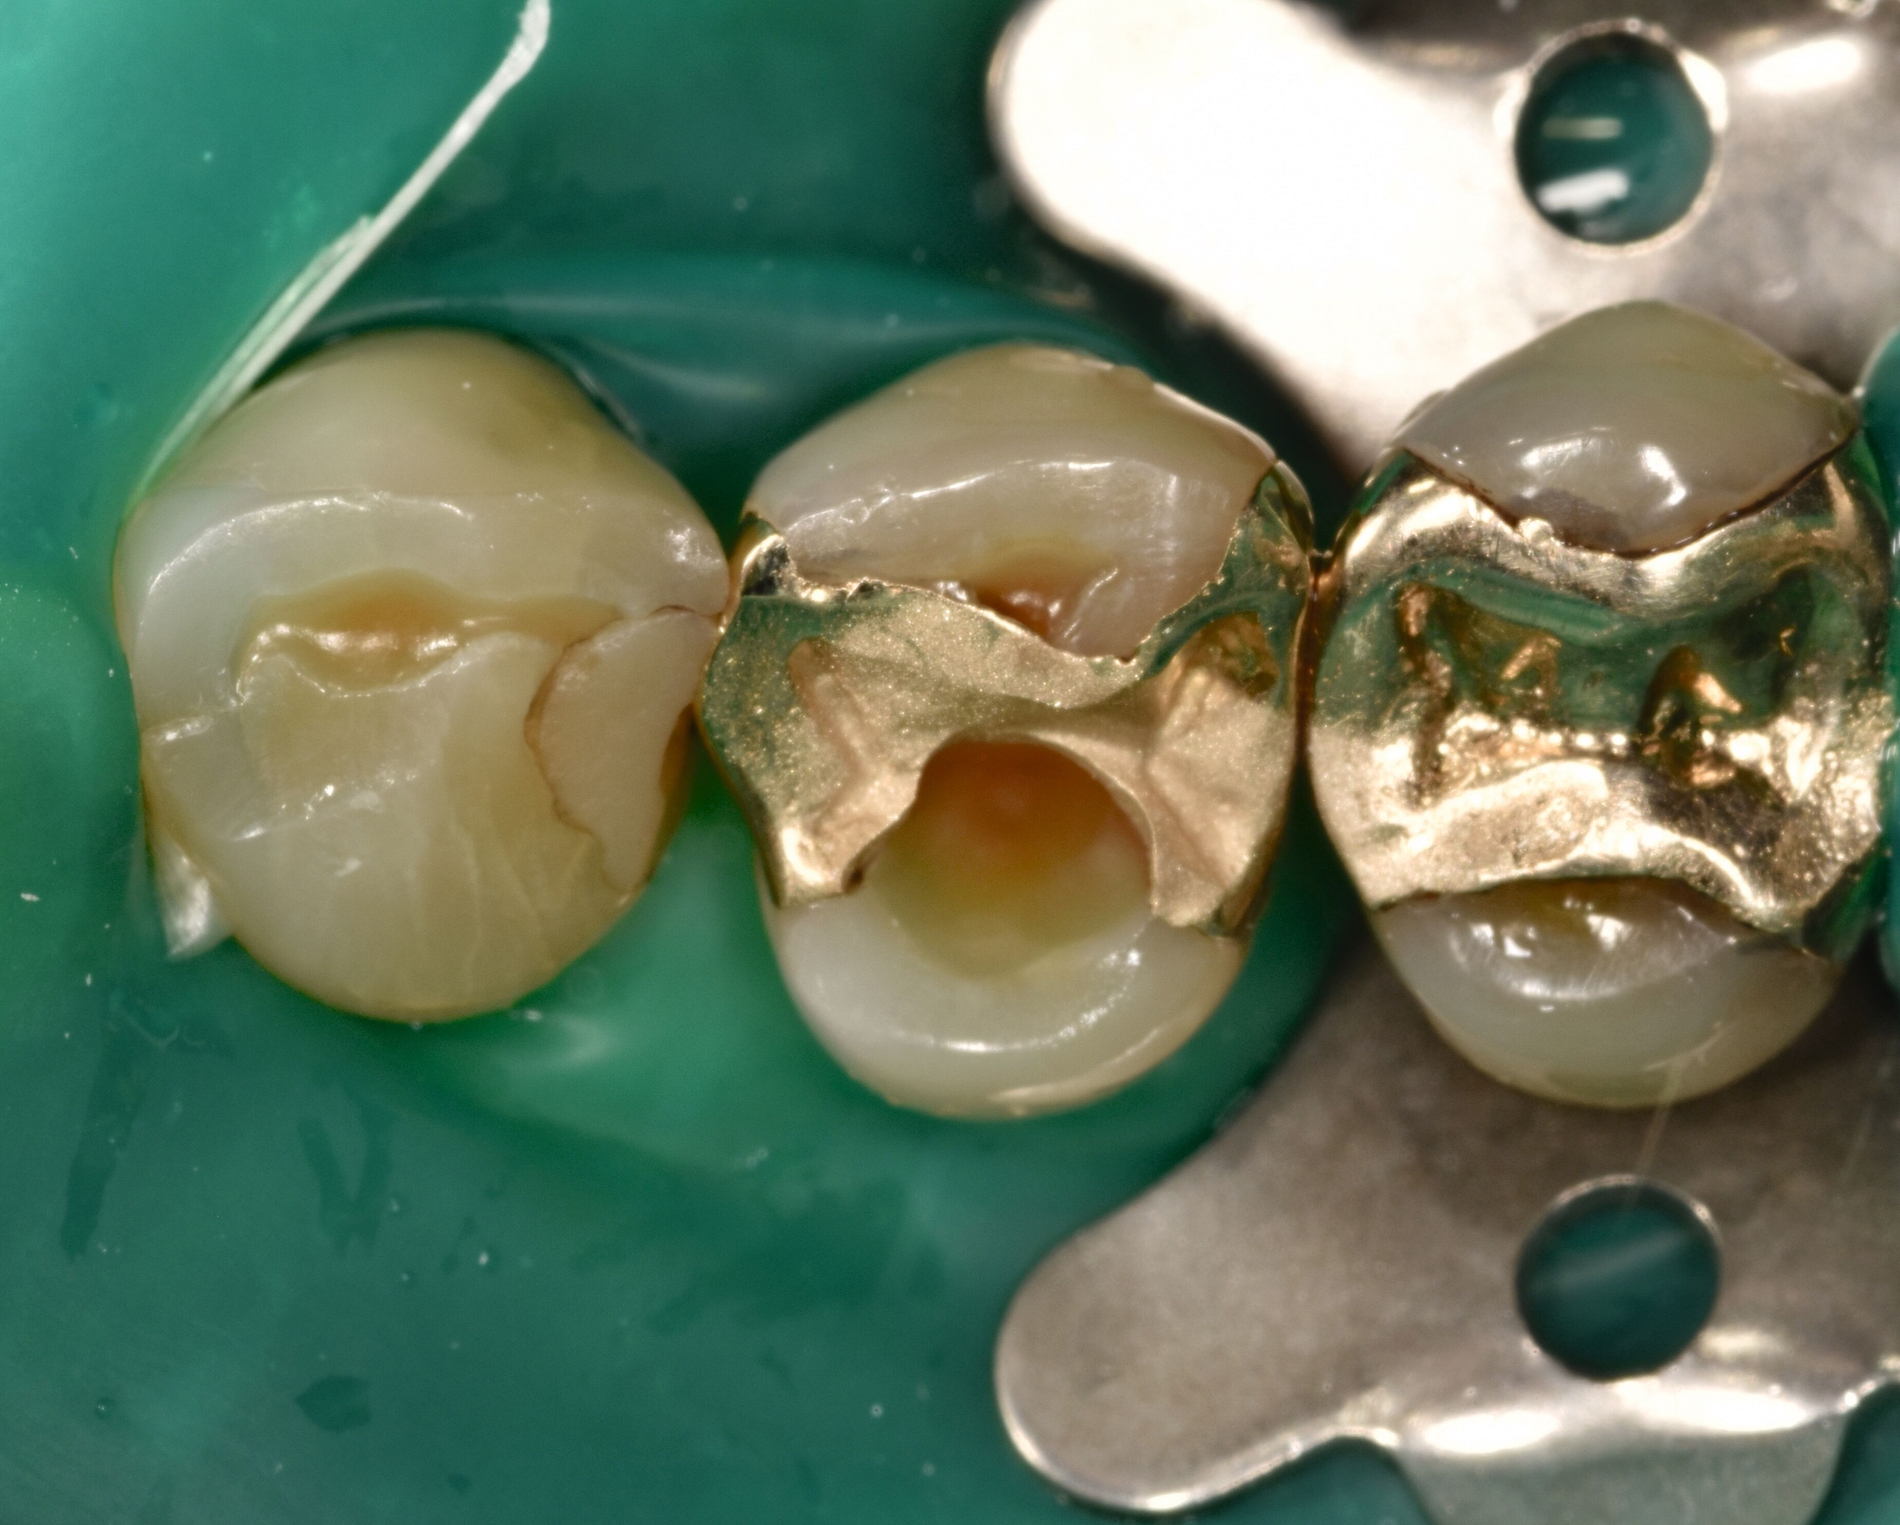

Aufgrund einer erwartungsgemäß erschwerten fotografischen Dokumentation bei der zahnärztlichen Behandlung in der mobilen Zahnmedizin wird die klinische Falldokumentation an einer Seniorin vorgenommen, deren Therapiefähigkeit und Eigenverantwortlichkeit nicht eingeschränkt war. Die 76-jährige Patientin stellt sich zur routinemäßigen Kontrolle in der Poliklinik für Zahnerhaltungskunde vor. Die allgemeine Anamnese ergab Zustand nach Meningeom, eine Quecksilber- und eine Birkenpollenallergie und einen erhöhten Blutdruck, der mit Lercanidipin eingestellt war. Am circa 20 Jahre alten Gussmetall-Inlay an Zahn 24 wurde dabei ein sondierbarer Randspalt festgestellt (Abbildungen 2a und 2b).

Nach Reinigung der Zähne und Bestimmung der Zahnfarbe wurde Kofferdam zur absoluten Trockenlegung angelegt. Mit rotierenden Instrumenten wurde ein Teil des Gussmetall-Inlays im sondierbaren Bereich entfernt und die Karies exkaviert (Abbildungen 2c und 2d). Anschließend wurden alle zu reparierenden Oberflächen (Gussmetall, Dentin und Schmelz) mit reinem Aluminiumoxid, Partikelgröße 50 µm (Rondoflex®/KaVo), unter Verwendung von Wasser abgestrahlt und danach gründlich mit Wasser abgespült (Abbildungen 2e und 2f). Die selektive Schmelzätzung erfolgte mit 37,5-prozentiger Phosphorsäure (Email Preparator®/Ultradent) für 30 Sekunden (Abbildung 2g). Nach Abspülen der Phosphorsäure mit Wasser wurde ein Universaladhäsiv (Clearfil Universal Bond Quick® / Kuraray Noritake) aufgetragen (Abbildung 2h, Glanz soll erhalten bleiben, Verdunstung einige Sekunden abwarten) und dann lichtpolymerisiert.